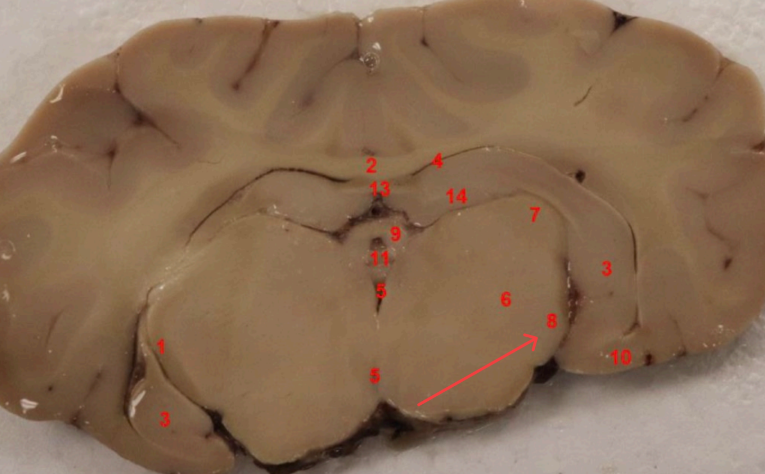

What nuclei is this, function?

Caudate Nucleus , motor control, voluntary movement planning, and procedural learning (habits)

what area is this, function?

nucleus accembus, reward, pleasure, addiction, and motivation.

what tract is this, ?

Cingulum bundle

what COMMISSURE i s this

genu of corpus callosum

what tract is this ? function?

septohypthalmic tract

what ventricle is this

lateral

what area is this

Olfactory Tubercle

what commisure is this

body of corpus callosum

septum pellucidum

what nuclei is this

Caudate nucleus

what capsule is this

external capsule

septohypothalamic tract

what cortex is this

piriform cortex, part of olfatcory system ( smell)

septum pellicidum

internal capsule

what nuclei is this ? function

Putamen, regulates motor control, including movement initiation, planning, and execution.

what is this

claustrum

what area is this?

extreme capsule

what nuclei is this?

Global Pallidus , regulates voluntary movement, suppresses unwanted motor activity, and influences reward/motivatio

what tract is this

Fornix

Global Pallidus

Putamen

Clustrum

Insula, internal sensation (interoception_

what cortex is this?

piriform cortex